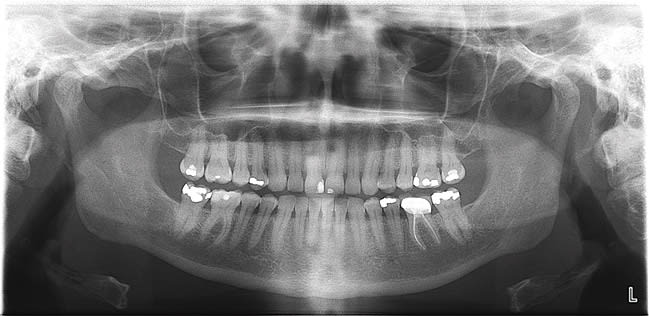

Both CCD and CMOS are solid-state digital technologies that use a one-step process. Sensors for both have multiple electron wells that correspond to picture elements (pixels). The electron wells are covered by a silicon layer. Incoming x-ray photons interact with (ionize) silicon atoms and the freed electrons are collected in the wells. As the electron charge is transferred to a readout photomultiplier (amplifier), it is moved to an analog-to-digital converter. From this electronic data, the software creates the radiolucent and radiopaque areas on the resultant image. The two technologies differ in the pixel readout mechanism, transistor location, and energy requirement. Both types of sensors are ready for reuse once the almost instantaneous readout is completed.5 For digital panoramic radiographs, the pixel array is two pixels wide and uses a scanning movement to acquire the image—similar to a standard photocopier, which actually uses the same technology. The image appears on the computer monitor within seconds of acquisition (Figure 1). Solid-state digital panoramic units are dedicated digital units that do not have analog film capability. Retrofit kits to convert film-based units to solid-state digital are available for some models.

Several optional features are available on digital panoramic units from various manufacturers. Features include: 1) variable arch shapes; 2) curved linear projections of the temporomandibular joints, maxillary sinuses, and cross sections of the jaws; 3) automatic exposure control; and 4) panoramic bitewings (Figure 2).8-12